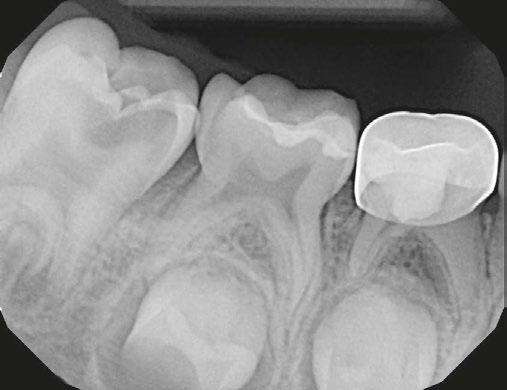

Several clinical solutions exist for primary anterior teeth with multisurface decay. Full coronal restoration of carious primary incisors may be indicated when caries is present on multiple surfaces, pulpal therapy is indicated, caries may be minor, but oral hygiene is very poor, or in a child with severe early childhood caries or a high caries risk diagnosis.1 Depending on the clinical scenario, a minimally invasive approach with the utilization of a high viscosity glass ionomer cement (HVGIC), with or without the combination of silver diamine fluoride (SDF) in a strip crown form, may pause the caries progression and provide an adequate clinical solution. Resin composite strip crowns have shown 80% retention rates and adequate parental satisfaction,1-4 although composite resin strip crowns have shown lower retention rates in teeth with decay involving three or more surfaces and particularly in children with a high caries risk4-6 (Figure 1). This could be from the continued high caries risk behaviors of the patient, as composite resin strip crowns in this population have shown to have increased inflamed marginal gingiva and gingival bleeding, increased plaque retention along the restoration, and loss of some restorative material.5,6

2: NuSmile® Anterior Zirconia crowns at 2-year follow up. Note the high amount of plaque accumulations along the untreated cuspid and existing stainless-steel crowns

This review discusses three clinical cases in which NuSmile® ZR (NuSmile, Houston, Texas) anterior pediatric zirconia crowns were the correct clinical decision in varying clinical scenarios.

A 2-year-old male who received full mouth dental rehabilitation (FMDR) under general anesthesia presented for his 6-month recall at 2-year post FMDR. He had significant plaque accumulations with poor oral hygiene along his existing stainless-steel crowns (SSCs) and non-treated teeth. Additionally, the patient had gingival bleeding and gingival inflammation

Figure 1: Occlusal films at recall visit in high caries risk patients showing loss of material and recurrent decay in composite resin strip crowns Figure

around these clinical sites. His anterior zirconia crowns showed healthy gingival margins with little-to-no plaque accumulations. This positive clinical finding is from the highly polished nature and biocompatibility of pediatric zirconia crowns. These restoration features limit plaque accumulations on the restoration and along the marginal gingiva, providing a localized positive aspect directly related to the choice of restorative material (Figure 2).